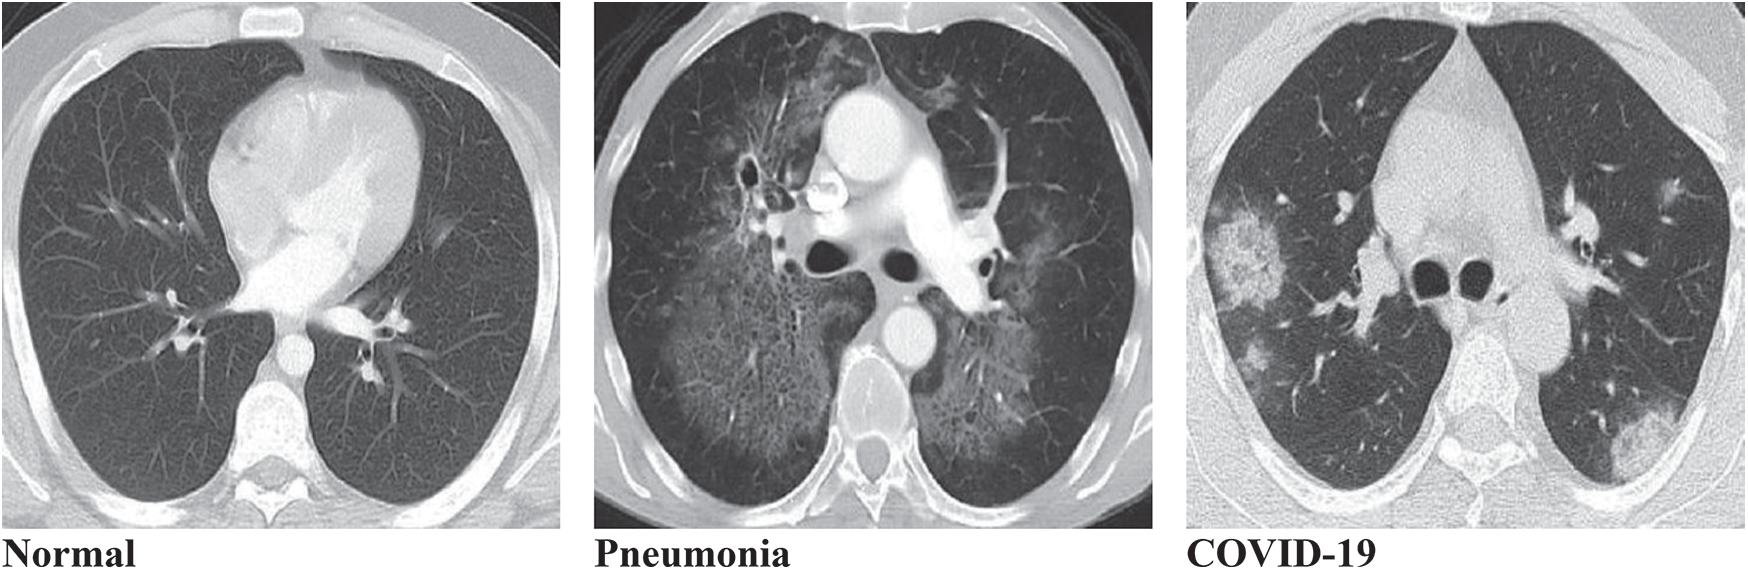

This study considers a dataset that contains lung disorders divided into three classes (Normal, Pneumonia, and COVID-19) which are determined by using CT images as shown in Fig. 1 below.

Figure 1: Typical three types of lungs CT image datasets. (a) Normal, (b) Pneumonia, (c) COVID-19

The patients prone to the epidemic were selected on the basis of the dataset. The CT images dataset is collected from two different sources, the first one is the Radiology Department of Nishtar Hospital Multan and Civil Hospital Bahawalpur, Pakistan, and the second one is a publicly free available medical imaging database known as Radiopaedia (https://radiopaedia.org/). For each class, 400 patients were selected to examine their lung disorder using CT images of size (620